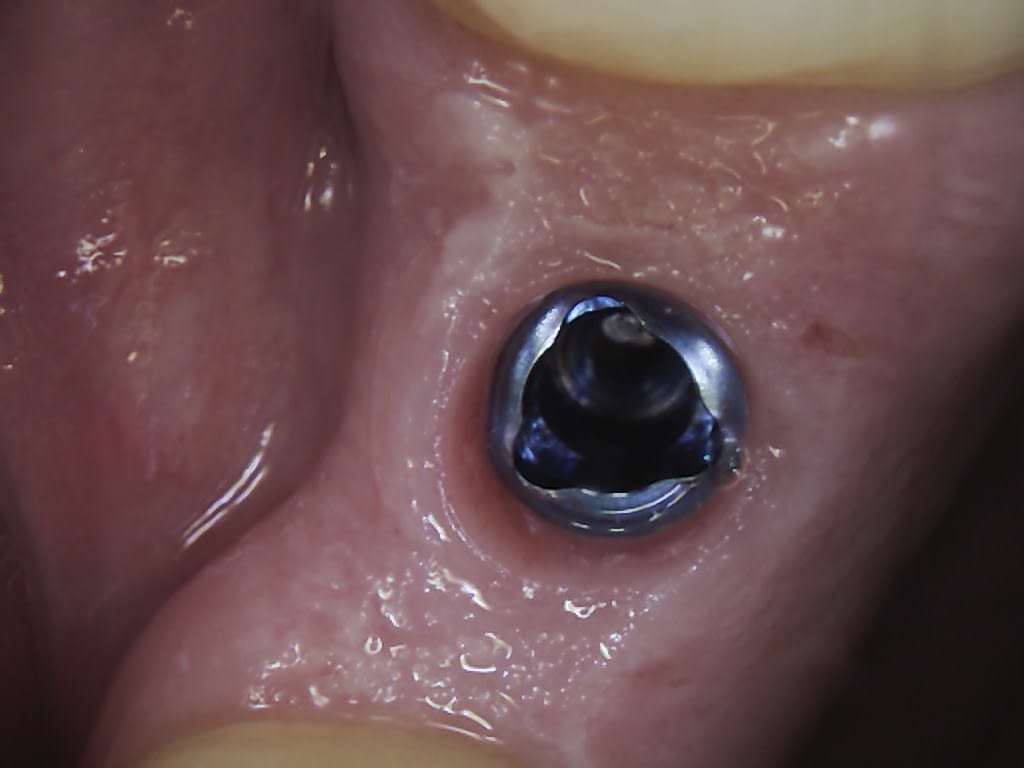

Patiente rencontrée ce matin, implant sur 26 posé il y a trois ans avec vis de cicat toujours en place......et début de cratérisation.

Reconnaissez vous la marque/modèle ?

Nobel replace en 5mm de diamètre